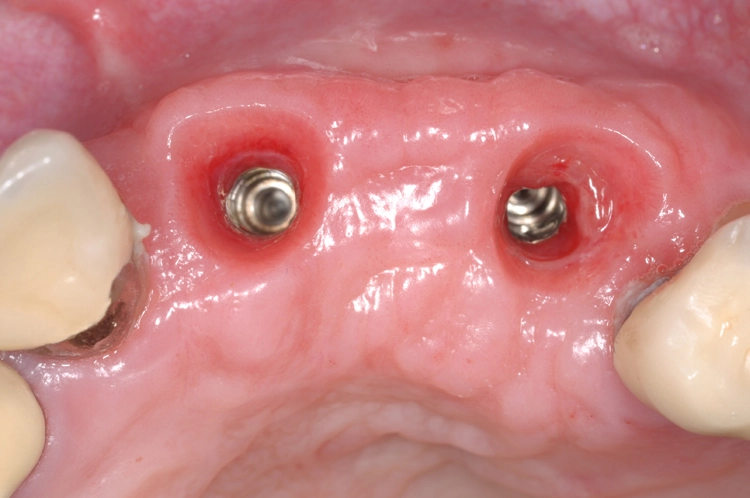

Nach einer viermonatigen Einheilphase erfolgte die Implantation von zwei Straumann® BLT Implantaten mit einer Länge von 12 mm und einem Durchmesser von 4,1 mm im Bereich des aufgebauten Knochens (Ausgangssituation siehe Abb. 8). Vor der Implantation fand vorbereitend eine Glättung der Oberfl äche statt, um scharfe Kanten zu beseitigen (Abb. 9). Für die korrekte prothetische Positionierung der Implantate kamen individuell gefertigte Orientierungsschablonen zum Einsatz, anschließend wurden die Implantate für eine verschraubte Brücke gesetzt (Abb. 10).

Die Abbildungen 11 und 12 dokumentieren das augmentative Relining, das zum Schutz vor Resorption und zur Konturaugmentation dienen soll. Dabei wurde eine Schicht bovines Knochenersatzmaterial (Straumann® XenoGraft) direkt auf den neu aufgebauten Knochen aufgetragen und mit Hilfe einer Kollagenmembran (Jason® membrane, Straumann) konturiert und vernäht. Damit legt man dem darunterliegenden neu aufgebauten Knochen einen Schutzpanzer an, der ihn einmal mehr vor Resorption schützt und die weitere Regeneration begünstigt.